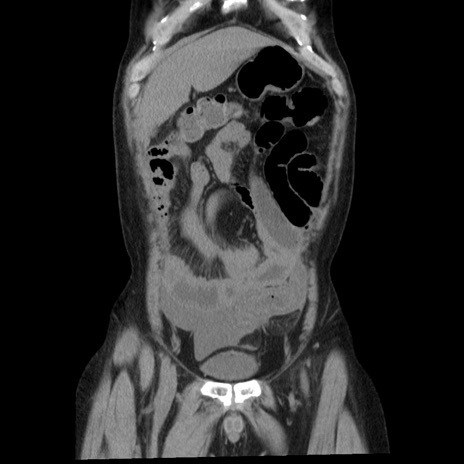

症例29(冠状断像)

【症例】40歳代男性

【現病歴】2日前から胃痛あり。徐々に周期的な激痛に変化した。本日になっても激痛があるため受診。

【身体所見】意識清明、BT 38-39℃台あり、腹部:膨満、やや硬、右下腹部に圧痛あり。

【データ】WBC 8500、CRP 23.26